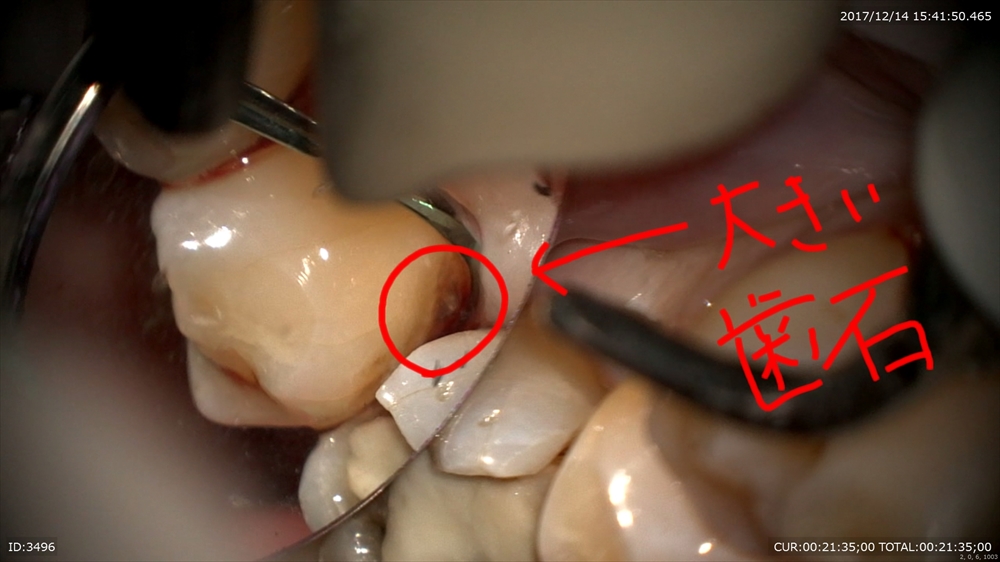

最後は歯周病の治療の御紹介

歯石やバイオフィルムを見つけてとる!!

これも!大きい!!

マイクロスコープで丁寧に行う事で患者さま無痛で寝ていました。